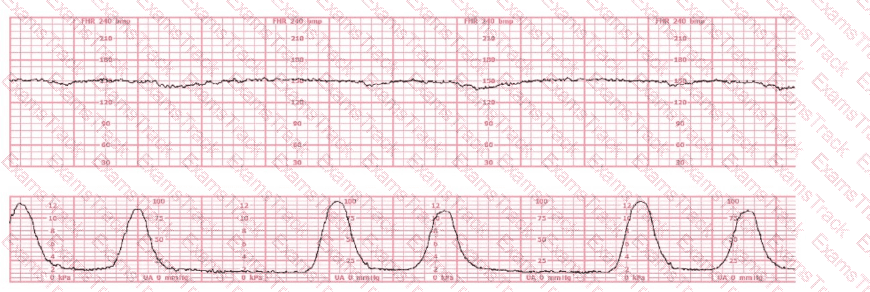

The fetal heart rate baseline is approximately 150 bpm, which is within the normal range of 110–160 bpm.

The tracing shows minimal variability (approximately 1–4 bpm amplitude). Minimal variability for a sustained period is categorized as a Category II pattern under NCC/NICHD classification.

No accelerations are present during the 20-minute representative segment.

There are no recurrent variable, no recurrent late, and no prolonged decelerations.

The tracing shows very frequent contractions—approximately every 1½ to 2 minutes, which meets the NCC definition of tachysystole when averaged over 10 minutes (more than 5 contractions in 10 minutes).